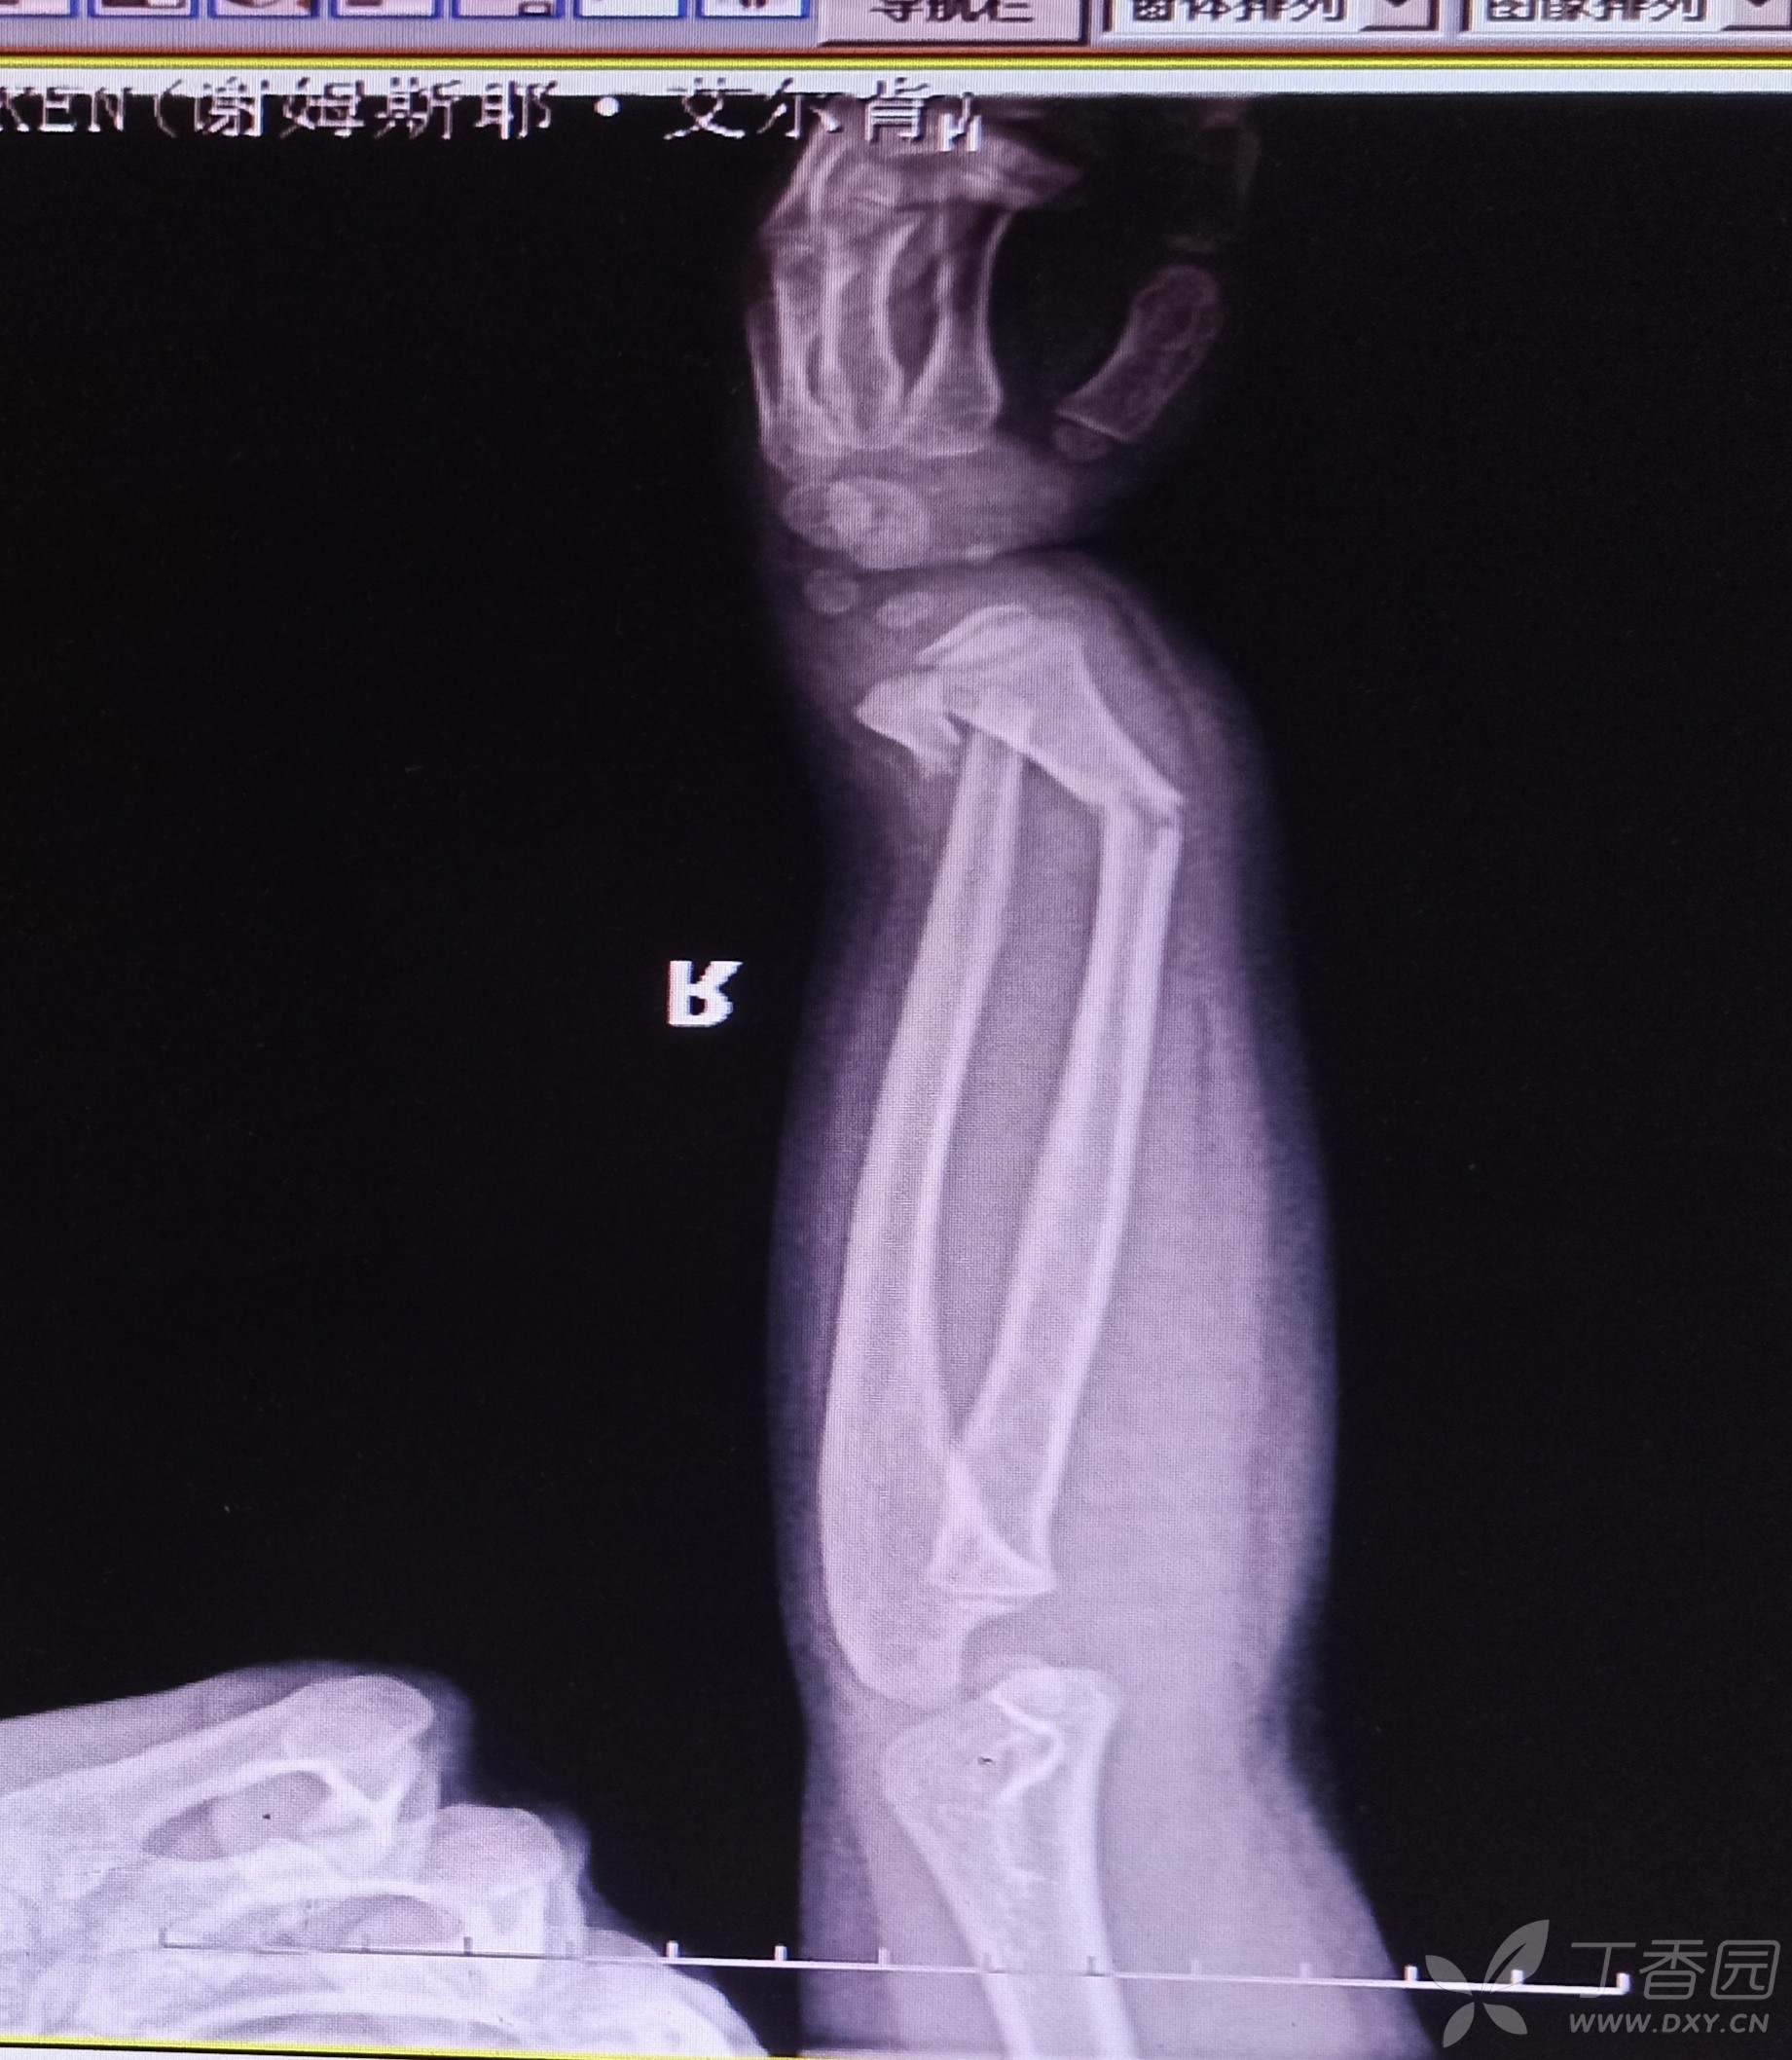

手法牵引复位拍片显示尺骨远端对位对线欠佳,下尺桡关节有分离,给予行弹性髓内钉内固定。遇到这样的各位老师保守还是手术?